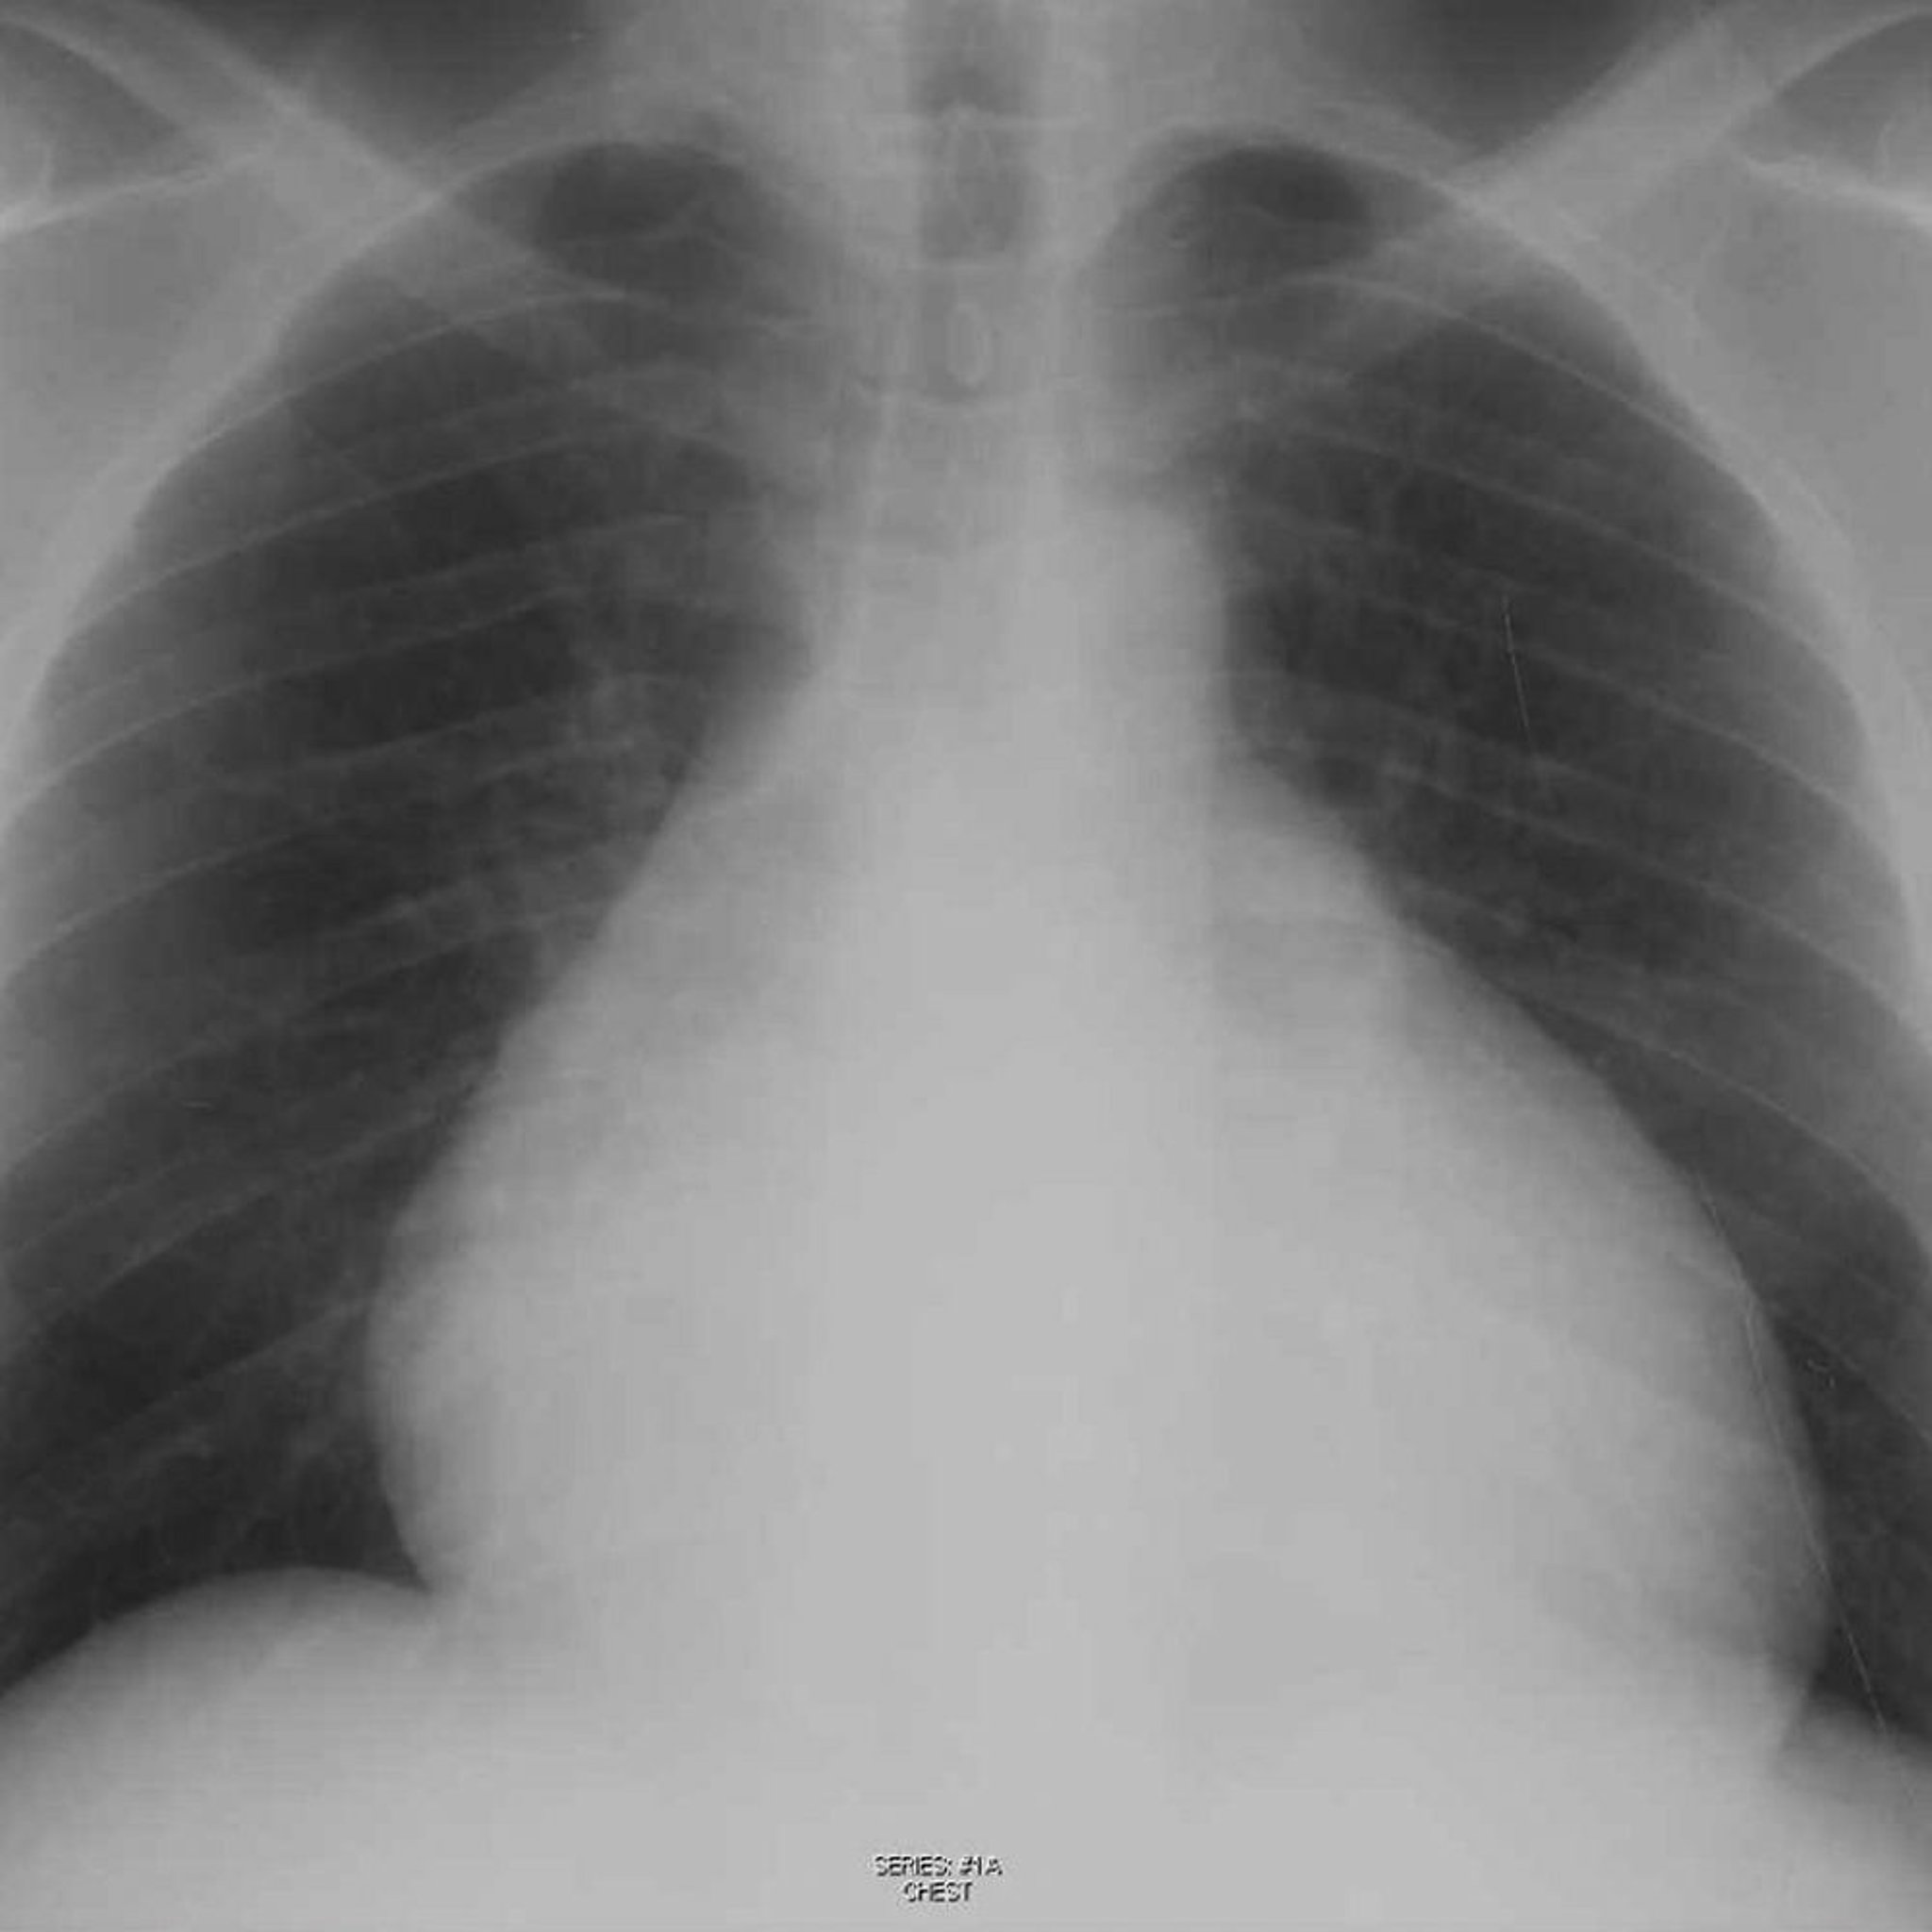

Radiografía torácica de un paciente con derrame pericárdico

Esta radiografía muestra una silueta cardíaca agrandada en un paciente con un derrame pericárdico.

© 2017 Elliot K. Fishman, MD.